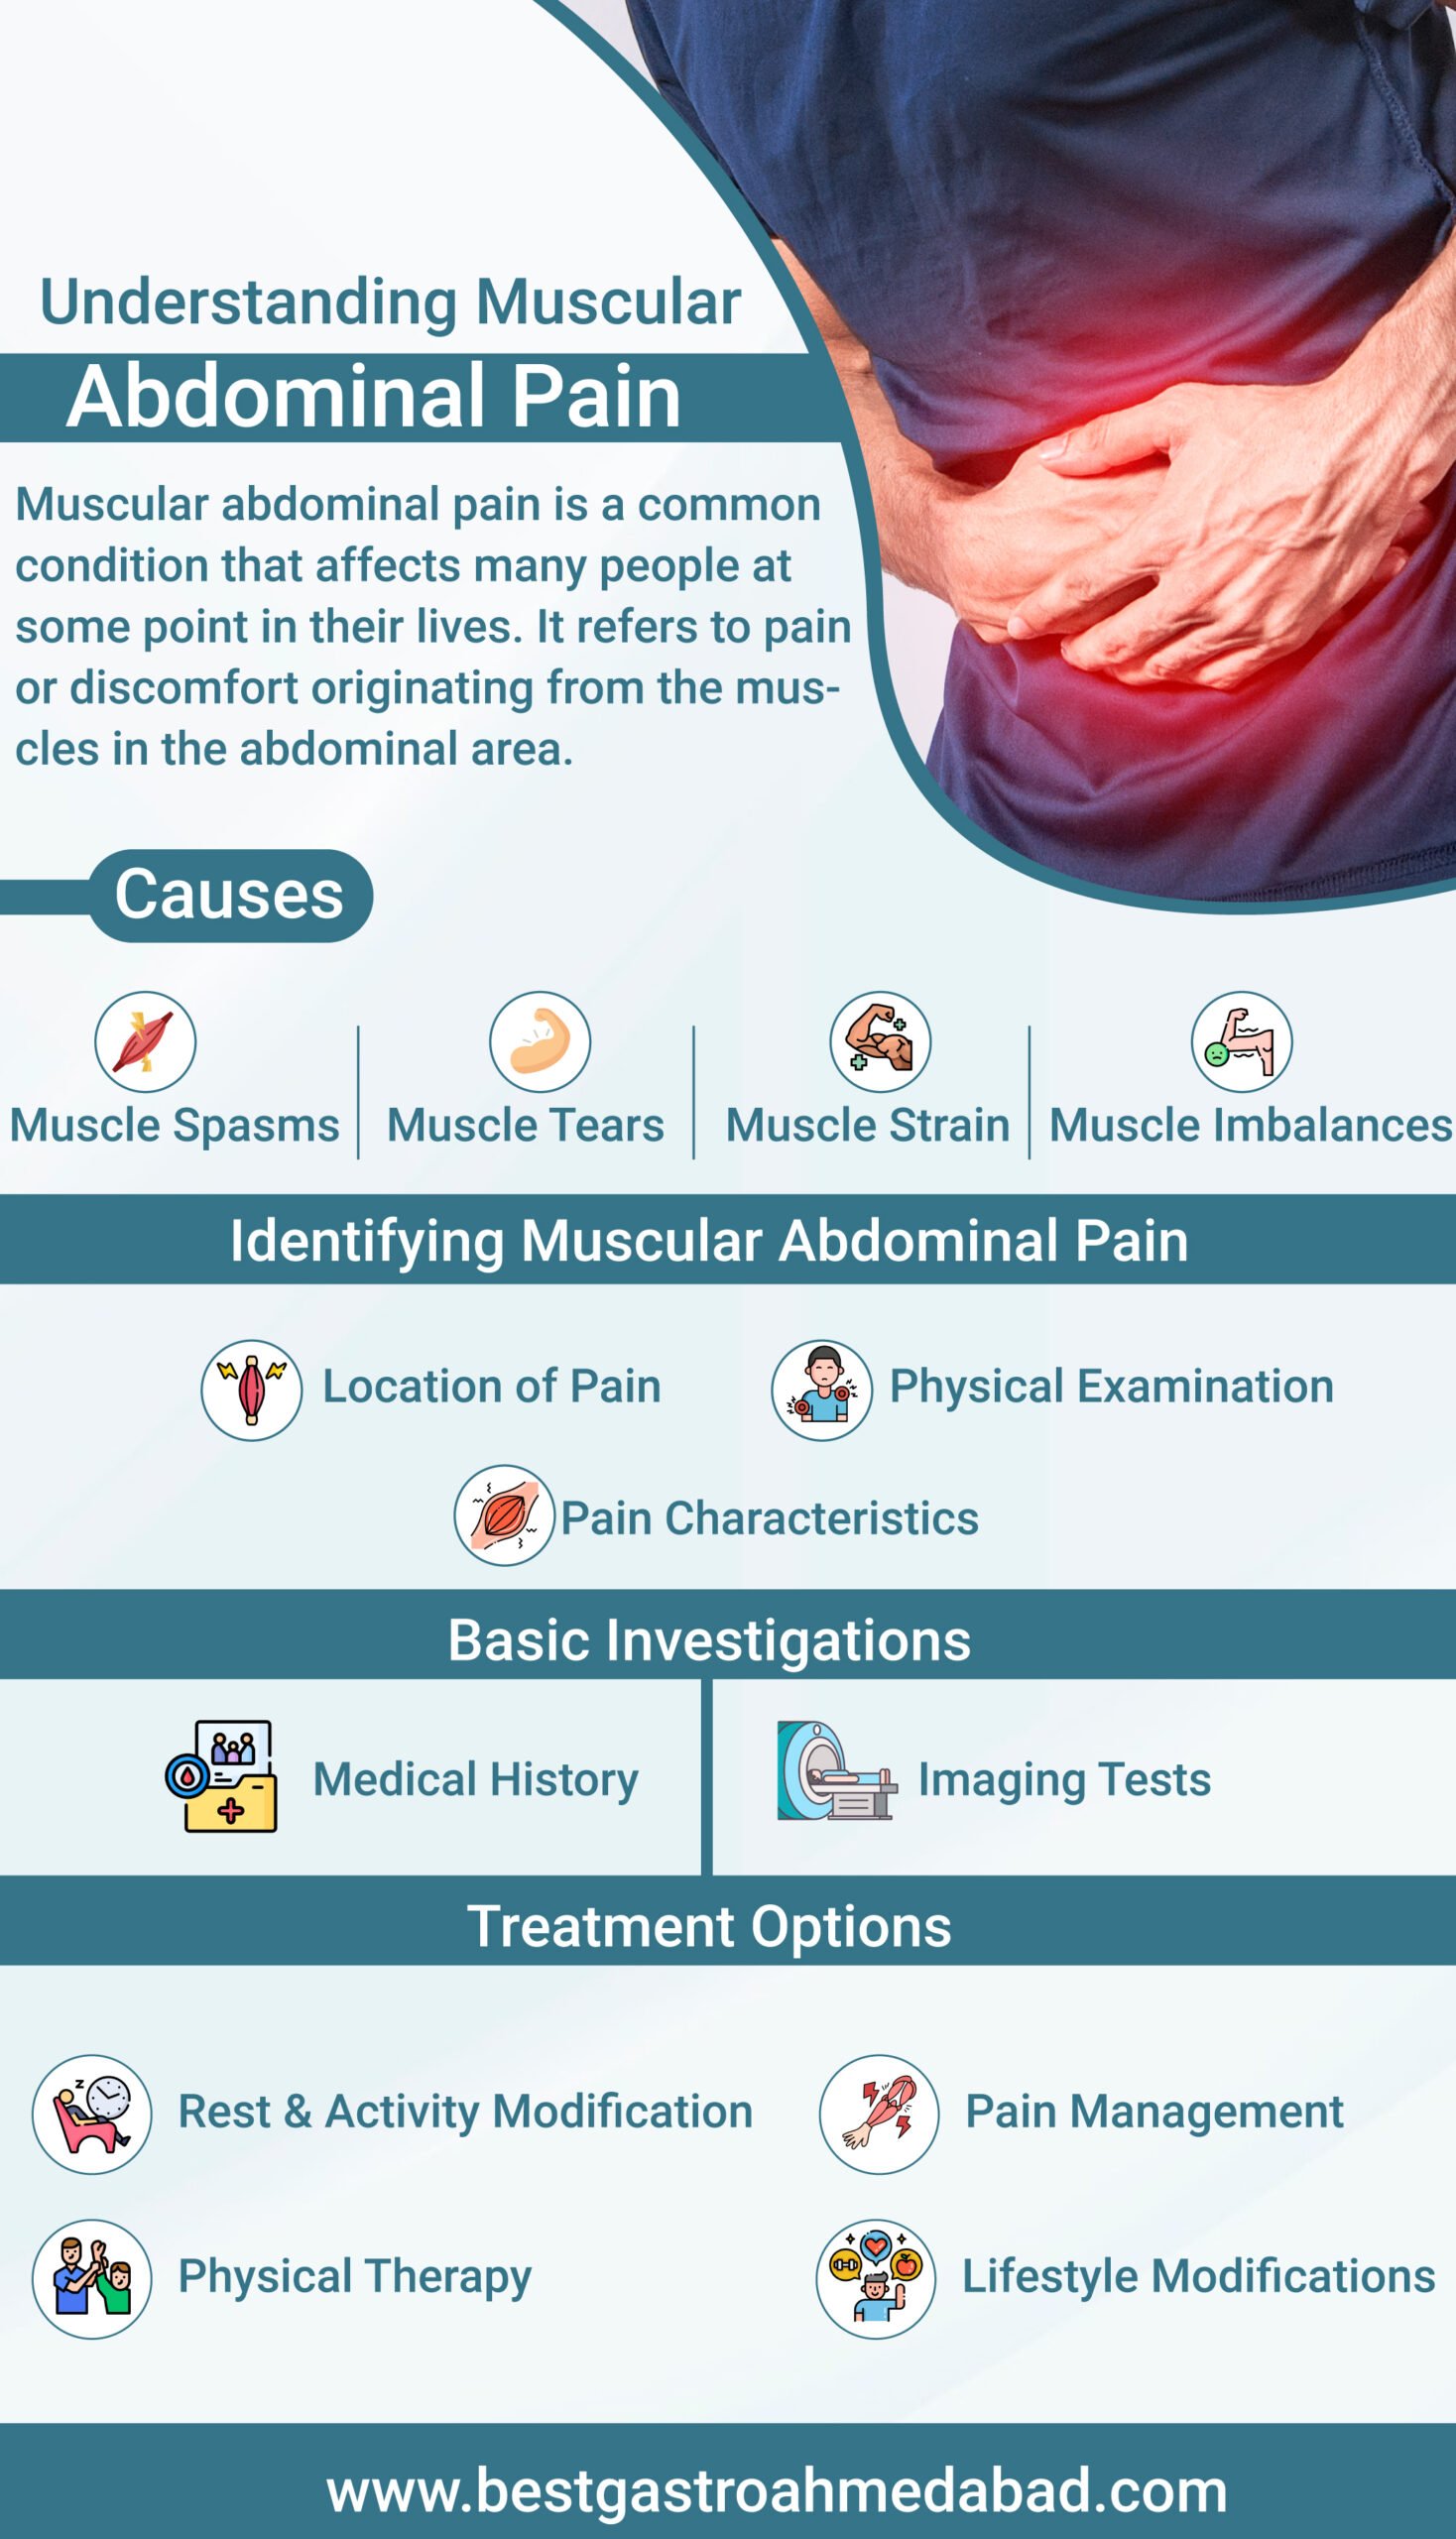

Muscles Pain In The Lower Abdomen Cause Symptoms Treatment

Understanding Muscular Abdominal Pain Causes Identification And

https://bestgastroahmedabad.com/wp-content/uploads/2023/06/Muscular-abdominal-pain-1-scaled.jpg